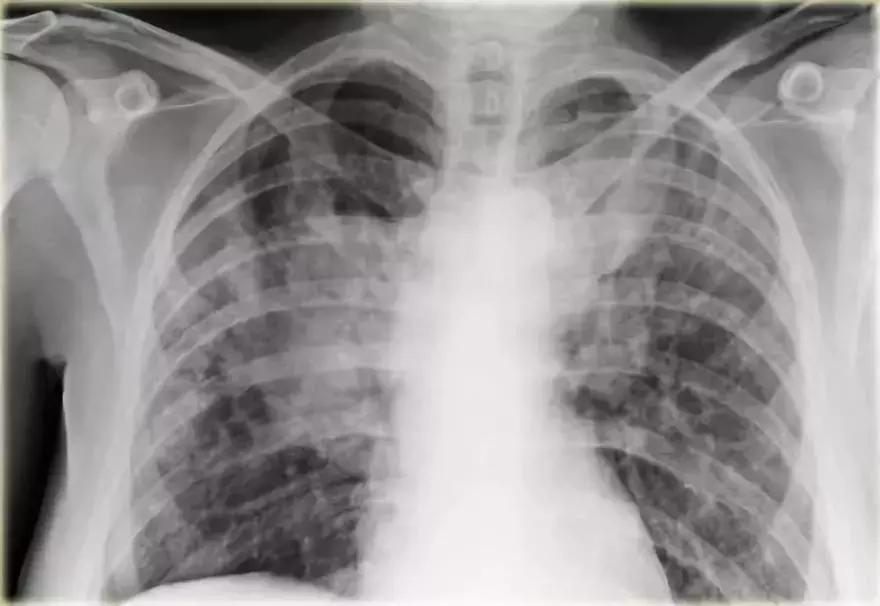

图9 弥漫性实变

充血性心力衰竭

影像学信息:

➢ 双侧肺门实变,伴有空气-支气管征及边界模糊

➢ 心脏大小增加

➢ 间质轻微肺纹

➢ 血管蒂可能增大